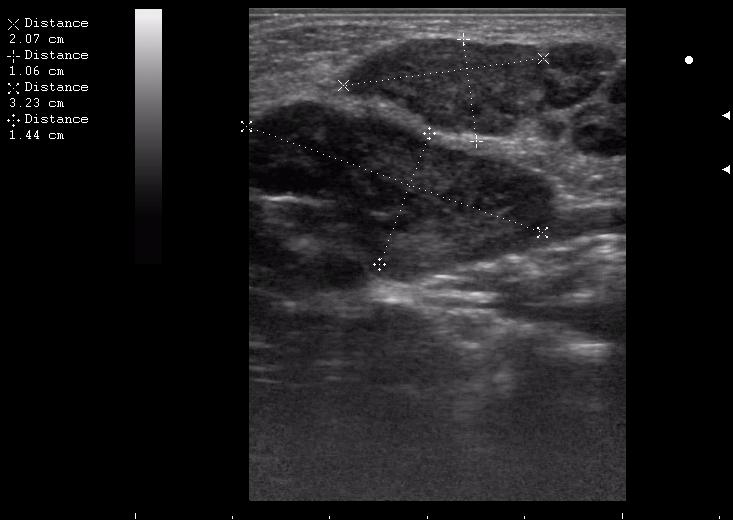

иногда я меряю так, и немножко ошибаюсь)